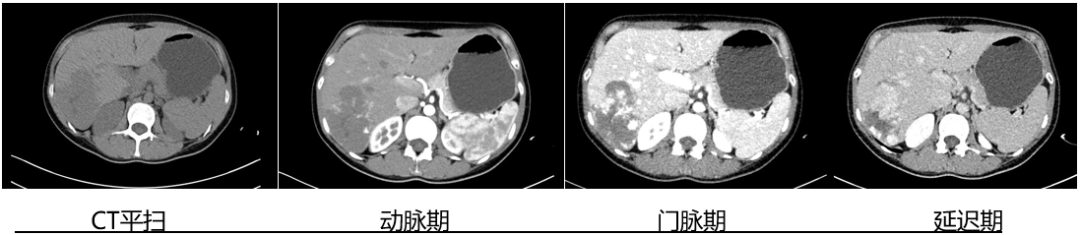

入院后,李建鋒主任醫師與秦蒙華主治醫師為申女士安排了腹部增強CT檢查,為了更清晰地掌握血管瘤的位置、大小及其與周圍組織的關系。

檢查結果顯示:肝臟內存在多個血管瘤。其中最大的一個位于肝臟右后葉的邊緣,大小約8.4厘米×5.6厘米;另一個較大的則位于肝左外葉邊緣,直徑約4.5厘米。